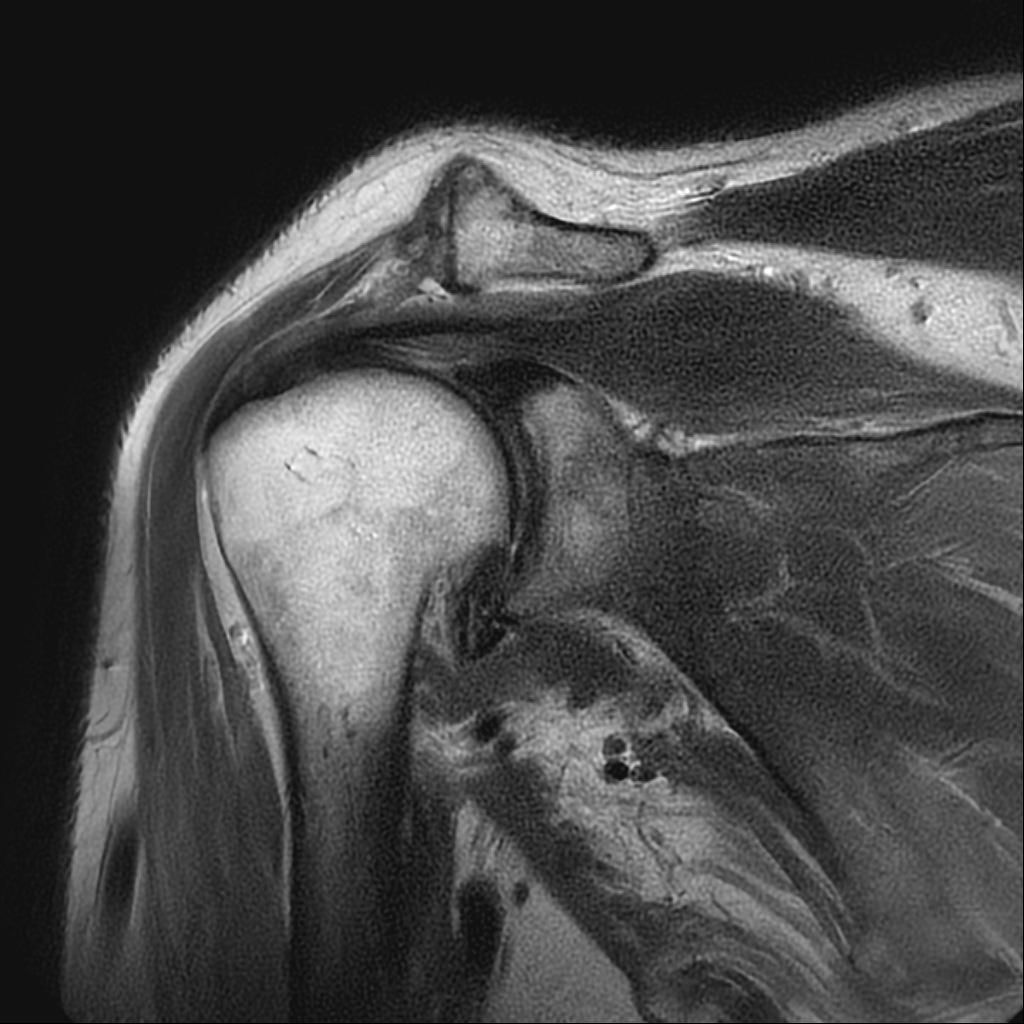

어깨 mri 상태인데 어디가 안 좋은가요?

안 좋다고 하시는데 어디 부위를 말하시는 거죠?

어디 부위인지 알곳 싶습니다.

어깨가 나쁜 부분이 어디죠?

• 1번 째 사진

해당사진으로 많은걸확인할수는없지만 회전근개손상을 의심해볼수있는데요 지속적으로 불편감이있다면 병원에서 검사와치료를받아보시길 바랍니다 감사합니다~

제가 직접 mri를 판독할 수는 없지만 일반적으로 어깨 mri에서 이상 소견이 자주 지적되는 부위는 회전근개 힘줄에 염증, 부분 파열, 손상이 흔합니다 또 견봉 아래 공간으로 충돌증후군이나 염증으로 공간이 좁아질 수 있습니다. 관절순은 탈구 벼력이 있으면 손상 가능성이 있어요 정확한 위치와 정도는 영상의학과 판독결과와 주치의 설명을 참고해야 합니다!

현재로썬 사진만으론 판단을 하긴 어렵지만 회전근개의 손상이 의심 갑니다.

회전근개 주변의 염증이나 손상이 발생하신 것으로 유추해볼 수 있겠습니다.

회전근개 손상은 어깨 관절 주변의 통증과 움직임 제한이 발생할 수 있으며,

완전 파열이 아닌 경우에는 보존적 치료를 우선 적용할 수 있습니다.